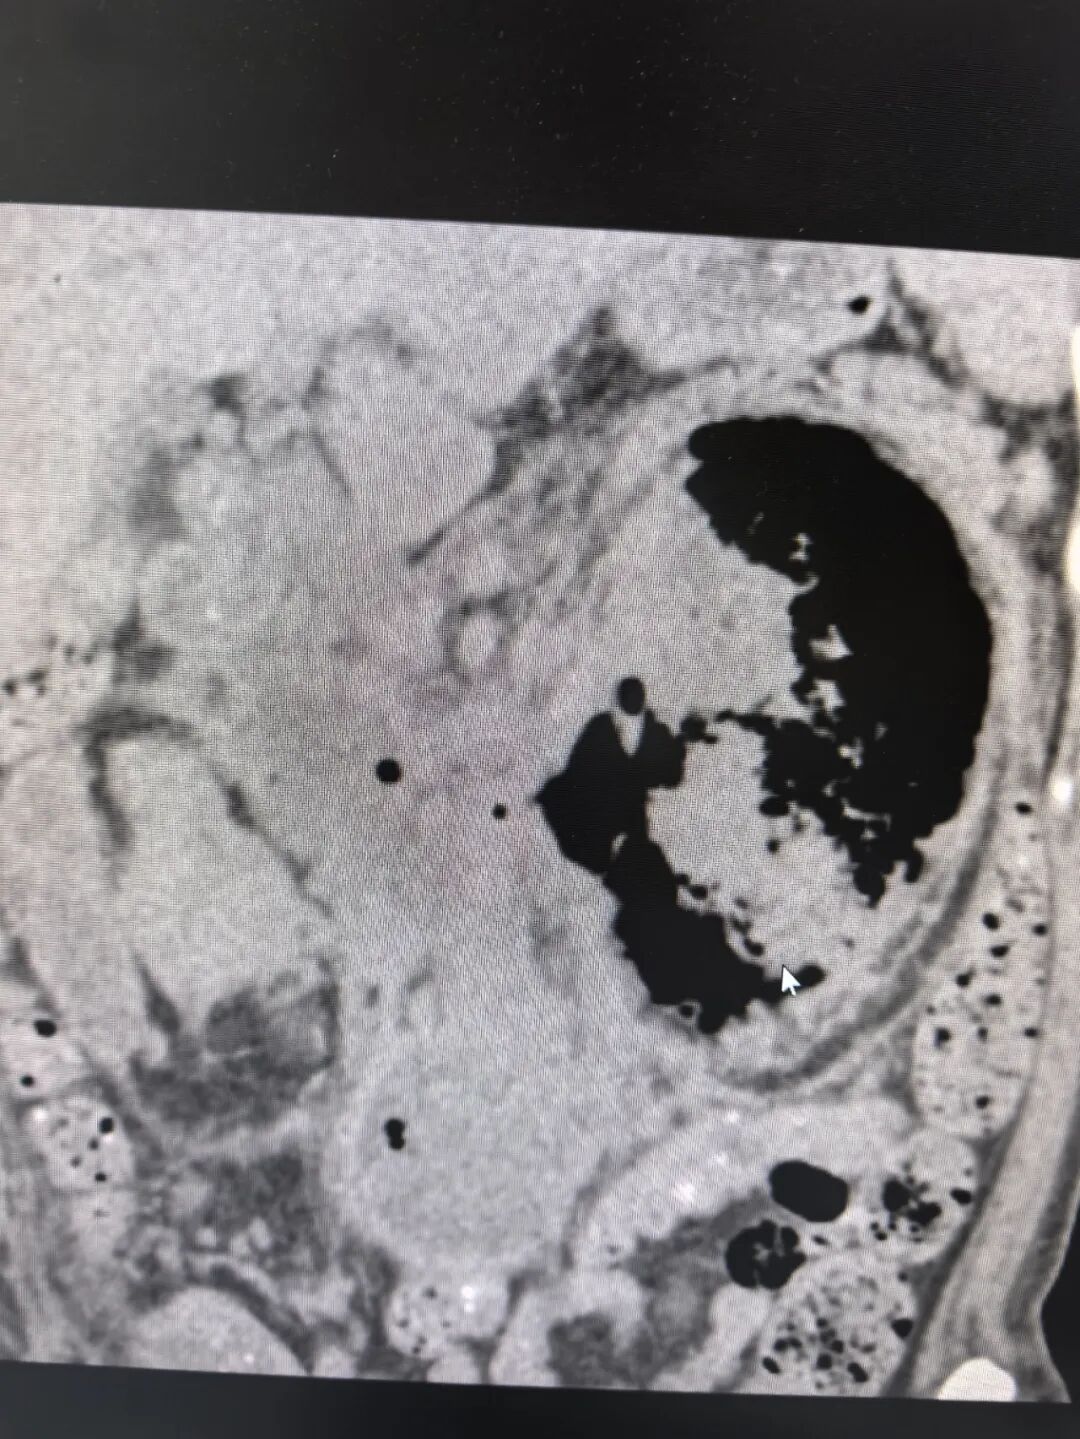

谢庆祥教授接诊后,对患者进行了全面而详细的检查。患者腹部CT见左肾积气严重、左肾大部分毁损、左肾盂内可疑内容物、右肾盂积水、腹膜后炎性积液致双侧输尿管腹段粘连、压迫。此外,患者还有双侧胸腔积液、肺部感染、肾功能不全、糖尿病、重度贫血、低蛋白等病症。进一步完善双肾CT增强检查,提示左肾多处脓肿伴积气,左肾实质毁损严重,左肾增强显影不理想。